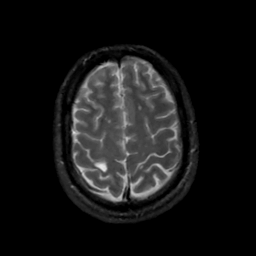

MR Study #12, May 12, 1991 -- Slice #40